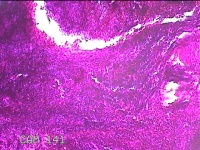

会阴部结节

性别

男

年龄

34岁

临床诊断

会阴部良性肿瘤

一般病史

发现会阴部结节1周。

标本名称

大体所见

灰白粉红色组织1.3x1.2x0.3cm一块,表面光滑,切面灰白粉红色。质软。

图2